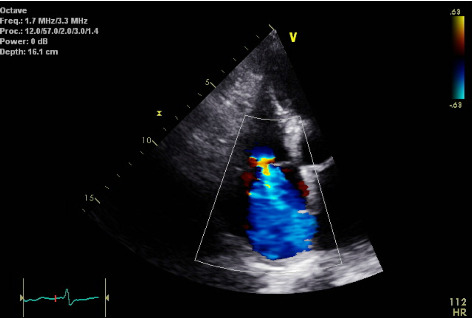

由维生素C缺乏引起的坏血病,在当代临床实践中越来越被认识到,特别是在脆弱人群中。尽管坏血病在历史上与航海探险有关,但在营养不良、酗酒、精神障碍和获取新鲜农产品有限的患者中,坏血病仍然存在。本报告提出两例坏血病诊断在低社会经济的城市设置,强调多样化和非典型的表现,这种情况。第一个病例涉及一名76岁女性,表现为精神状态改变和肺动脉高压,最终归因于严重的维生素C缺乏。超声心动图显示肺动脉压36毫米汞柱和严重的三尖瓣反流。经过全面的评估,结合营养不良和神经精神症状的证据,诊断为坏血病,血清维生素C水平无法检测。大剂量静脉补充维生素C可显著改善临床症状,缓解心肺功能异常。第二个病例描述了一个68岁的男性酒精使用障碍,表现为晕厥、贫血和全身炎症。实验室检查显示白细胞增多,急性肾损伤,铁蛋白升高,铁结合能力检测不到。营养检查发现严重的维生素C缺乏症(0.2 mg/dL)。口服维生素C补充剂可改善炎症标志物、贫血和总体健康状况。这些病例强调了考虑坏血病的重要性,患者无法解释的全身性症状和营养不良。早期诊断和及时治疗补充维生素C可导致完全康复和防止严重并发症。临床医生应保持对坏血病的高度怀疑,特别是在具有非典型临床表现的高危人群中。

Scurvy, caused by vitamin C deficiency, is increasingly recognized in contemporary clinical practice, particularly among vulnerable populations. Despite its historical association with maritime exploration, scurvy persists in patients with malnutrition, alcoholism, psychiatric disorders, and limited access to fresh produce. This report presents two cases of scurvy diagnosed in a low socioeconomic urban setting, emphasizing the diverse and atypical manifestations of this condition. The first case involves a 76-year-old female presenting with altered mental status and pulmonary hypertension, ultimately attributed to severe vitamin C deficiency. Echocardiography revealed a pulmonary artery pressure of 36 mmHg and severe tricuspid regurgitation. A thorough evaluation, combined with evidence of malnourishment and neuropsychiatric symptoms, led to the diagnosis of scurvy, confirmed by undetectable serum vitamin C levels. High-dose intravenous vitamin C supplementation resulted in marked clinical improvement and resolution of cardiopulmonary abnormalities. The second case describes a 68-year-old male with alcohol use disorder presenting with syncope, anemia, and systemic inflammation. Laboratory tests revealed leukocytosis, acute kidney injury, elevated ferritin, and undetectable iron-binding capacity. A nutritional workup identified severe vitamin C deficiency (0.2 mg/dL). Oral vitamin C supplementation improved inflammatory markers, anemia, and general well-being. These cases highlight the importance of considering scurvy in patients with unexplained systemic symptoms and malnutrition. Early diagnosis and prompt treatment with vitamin C supplementation can lead to full recovery and prevent severe complications. Clinicians should maintain a high index of suspicion for scurvy, especially in at-risk populations with atypical clinical presentations.